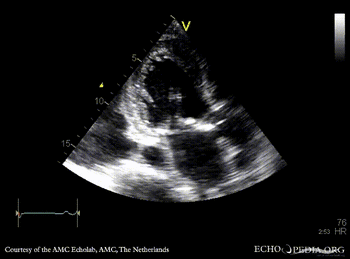

PSAX: aortic bioprosthesis